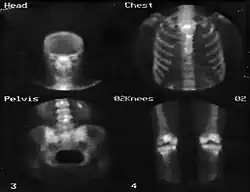

Figura 5: Exemplo de uma imagem de câmara gama de ossos de um paciente

Também é possível obter uma sequência de imagens dinâmicas e sincronizá-las com outros sinais como, por exemplo, um eletrocardiograma, de forma a gerar imagens do coração durante a sístole e a diástole.[3] A figura 5 apresenta um exemplo de imagem obtida por uma câmara gama.